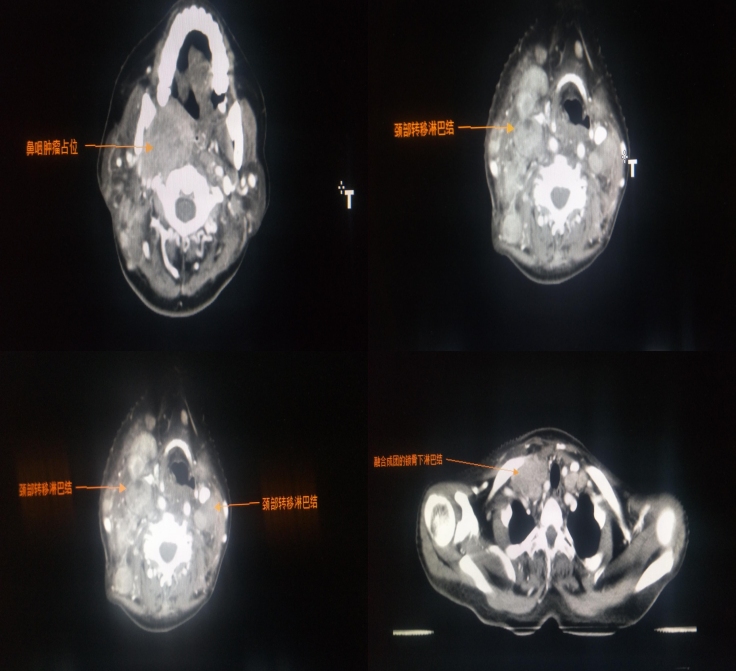

患者于2019年3月前后无明显诱因发现右颈肿物,2X2cm,质硬,无压痛,活动性差。曾于内蒙古国际蒙医院行颈部淋巴结穿刺活检,病理提示颈部淋巴结转移癌。鼻咽镜检查确诊鼻咽癌,患者仅口服蒙药对症治疗。后就诊于北京301医院,建议行放化疗,患者拒绝。2020年初患者颈部肿块增大,伴疼痛、吞咽困难,伴右眼视力下降、右耳失聪,再次就诊于内蒙古国际蒙医院,对症止疼治疗。2020年6月患者病情加重,为进一步治疗收入院。

入院后完善化验、检查,查体患者右眼不能外展,视力下降,左眼活动正常,视力正常。双颈多发淋巴结肿大,质韧,活动性差,融合成团,右侧淋巴结最大径13X11cm,左侧淋巴结最大径10X9cm。

2020年6月16日放疗定位,CT示右侧咽隐窝及咽后壁见巨大软组织肿块影,邻近颞骨岩部、枕髁、翼内板、翼外板、蝶窦后壁骨质破坏,双侧颌下、下颌下、耳前、耳后及颈部、右侧锁骨上、锁骨下多处淋巴结肿大。

初步诊断:

鼻咽鳞状细胞癌 未分化型;

侵犯颅底、颞部脑膜、右侧翼腭窝、右侧腮腺

侵犯II、III、IV、VI颅神经

双侧颈部淋巴结转移

右侧锁骨上、锁骨下淋巴结转移

诊断分期:cT4N3M0 IVb期